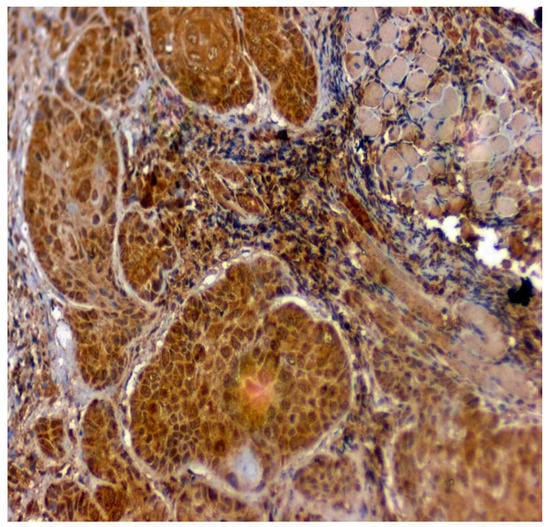

Figure 6.

IHC for CA1 in OSCC samples (under 20× magnification).

Positive immunoexpression for CA 1 was found in 70.4% (88/125). Among the 40 patients with OSCC, CA 1 overexpression was found in 75% (30/40), and among the OSMF patients, CA 1 overexpression was found in 77.8% (56/72) compared to 15.4% (2/13) of normal, which was found to be statistically significant (p = 0.000; χ2 = 21.169) (Table 3). Based on different degrees of epithelial abnormalities, we found a statistically significant association (p = 0.025; χ2 = 11.144). Our results showed epithelial atrophy among the OSMF patients showing positive CA 1 overexpression. There was no significant association between CA 1 expression and degrees of inflammation, fibrosis and vascularity. Figure 4 shows the negative immunoexpression of CA1 in normal samples. Figure 5 shows the CA 1-positive immunoexpression in epithelial cells in OSMF samples, with cytoplasmic and nuclear positivity. In OSCC samples, CA 1 demonstrates strong cytoplasmic and nuclear positivity in malignant epithelial cells (Figure 6).